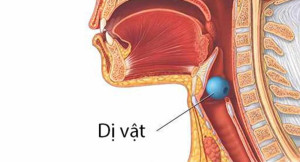

Khi nhắc đến dị vật đường thở chúng ta thường nghĩ ngay đến đối tượng là trẻ em, người già nhưng hóc dị vật có thể xảy ra với bất kỳ ai nếu chúng ta...